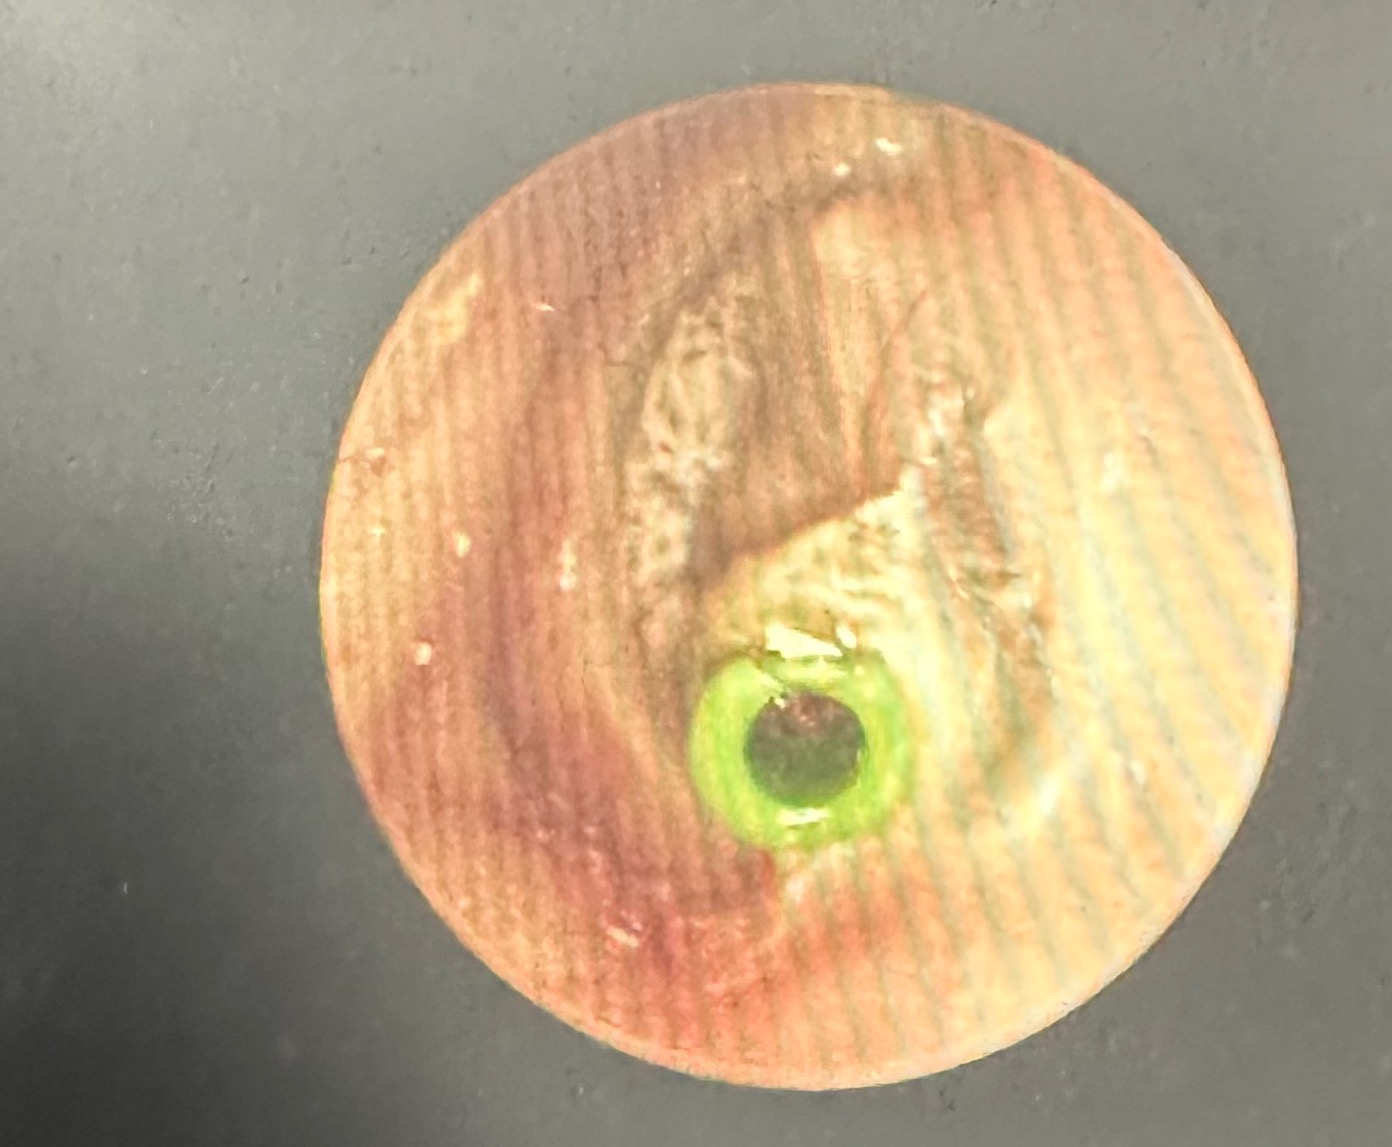

저의 고막에 환기관을 넣은 사진입니다. 컴퓨터의 사진을 찍어 온것이라 화소가 좋지 않아 보이네요.